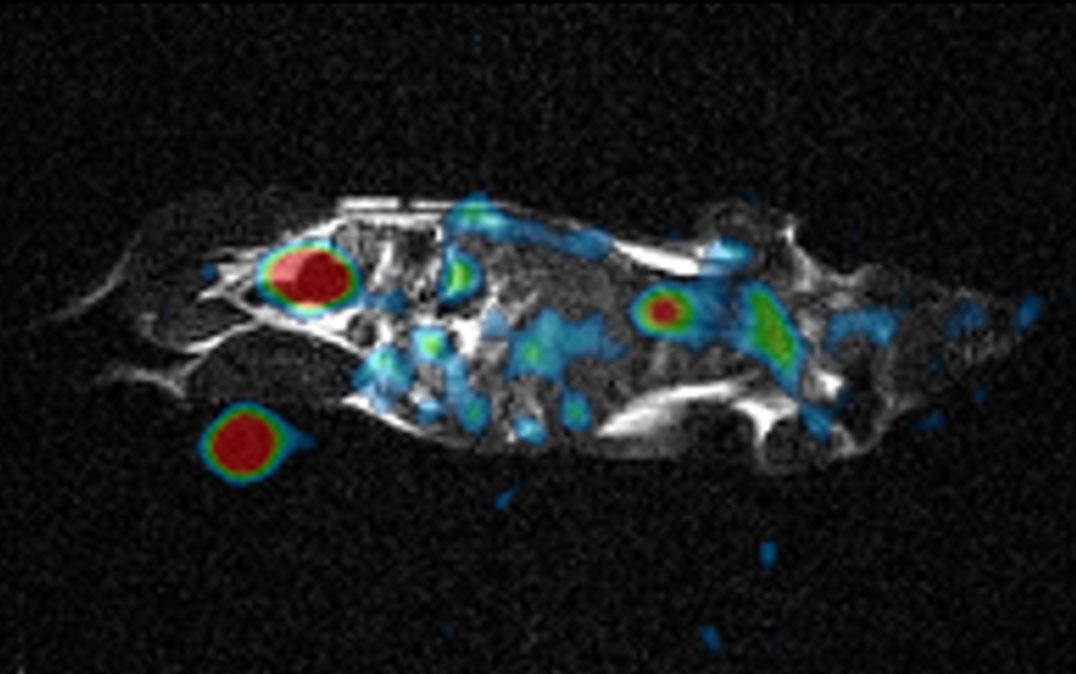

その検証として、磁場強度1.5テスラの四肢撮像用1H-MRI装置に開発したアドオン型23Na-MRI装置を装着し、マウス生体内の1Hと23NaをMRIで画像化することに成功しました。